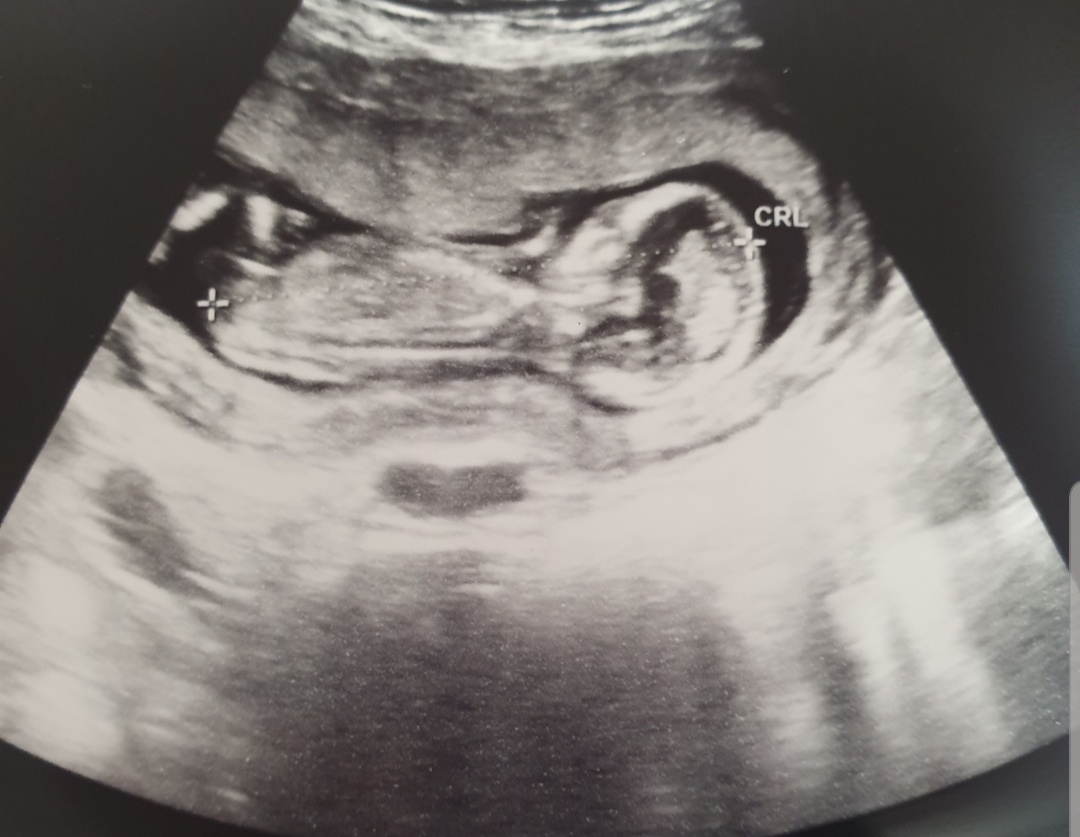

I think boy as slightly raised as is that stacking above? Baby is slightly turned though. Please let me know. Thanks :)

I think I answered this already but I don't think this pic is clear enough for me to guess on

At 14+, do you have a potty shot?